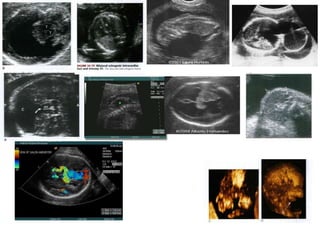

Ventriculomegaly

US Findings:

>10 mm diameter

> 3 mm choroid seperation

from medial wall

โ€œdangling choroidโ€

Choroid plexus Hangs

independently from

ventricle